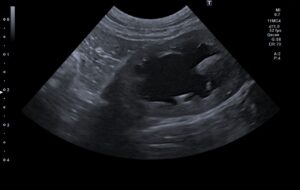

検査の結果、左の尿管結石と閉塞が見られました。

術後のエコーで腎臓の腎盂拡張は改善されています。